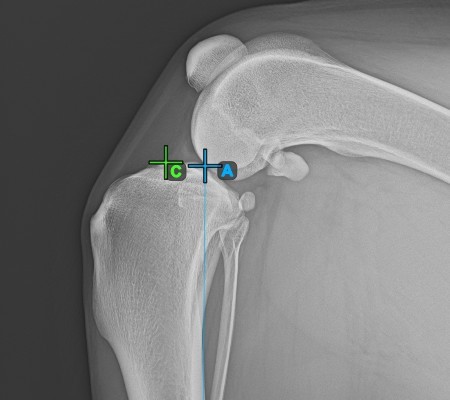

Start the measurement by marking the Eminentia Intercondylaris, which is located on the joint connecting the femur and the tibia.

The image below depicts the usual placement of the Eminentia Intercondylaris point.